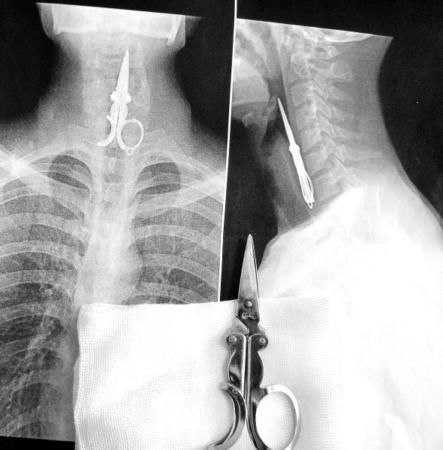

医生用间接喉镜检查时看到,剪刀尖端朝向林某的会厌喉面,剪刀柄全部进入食管内。给林某做了颈胸部拍片,发现卡在他食管中的剪刀长约9厘米,最宽处约4厘米。